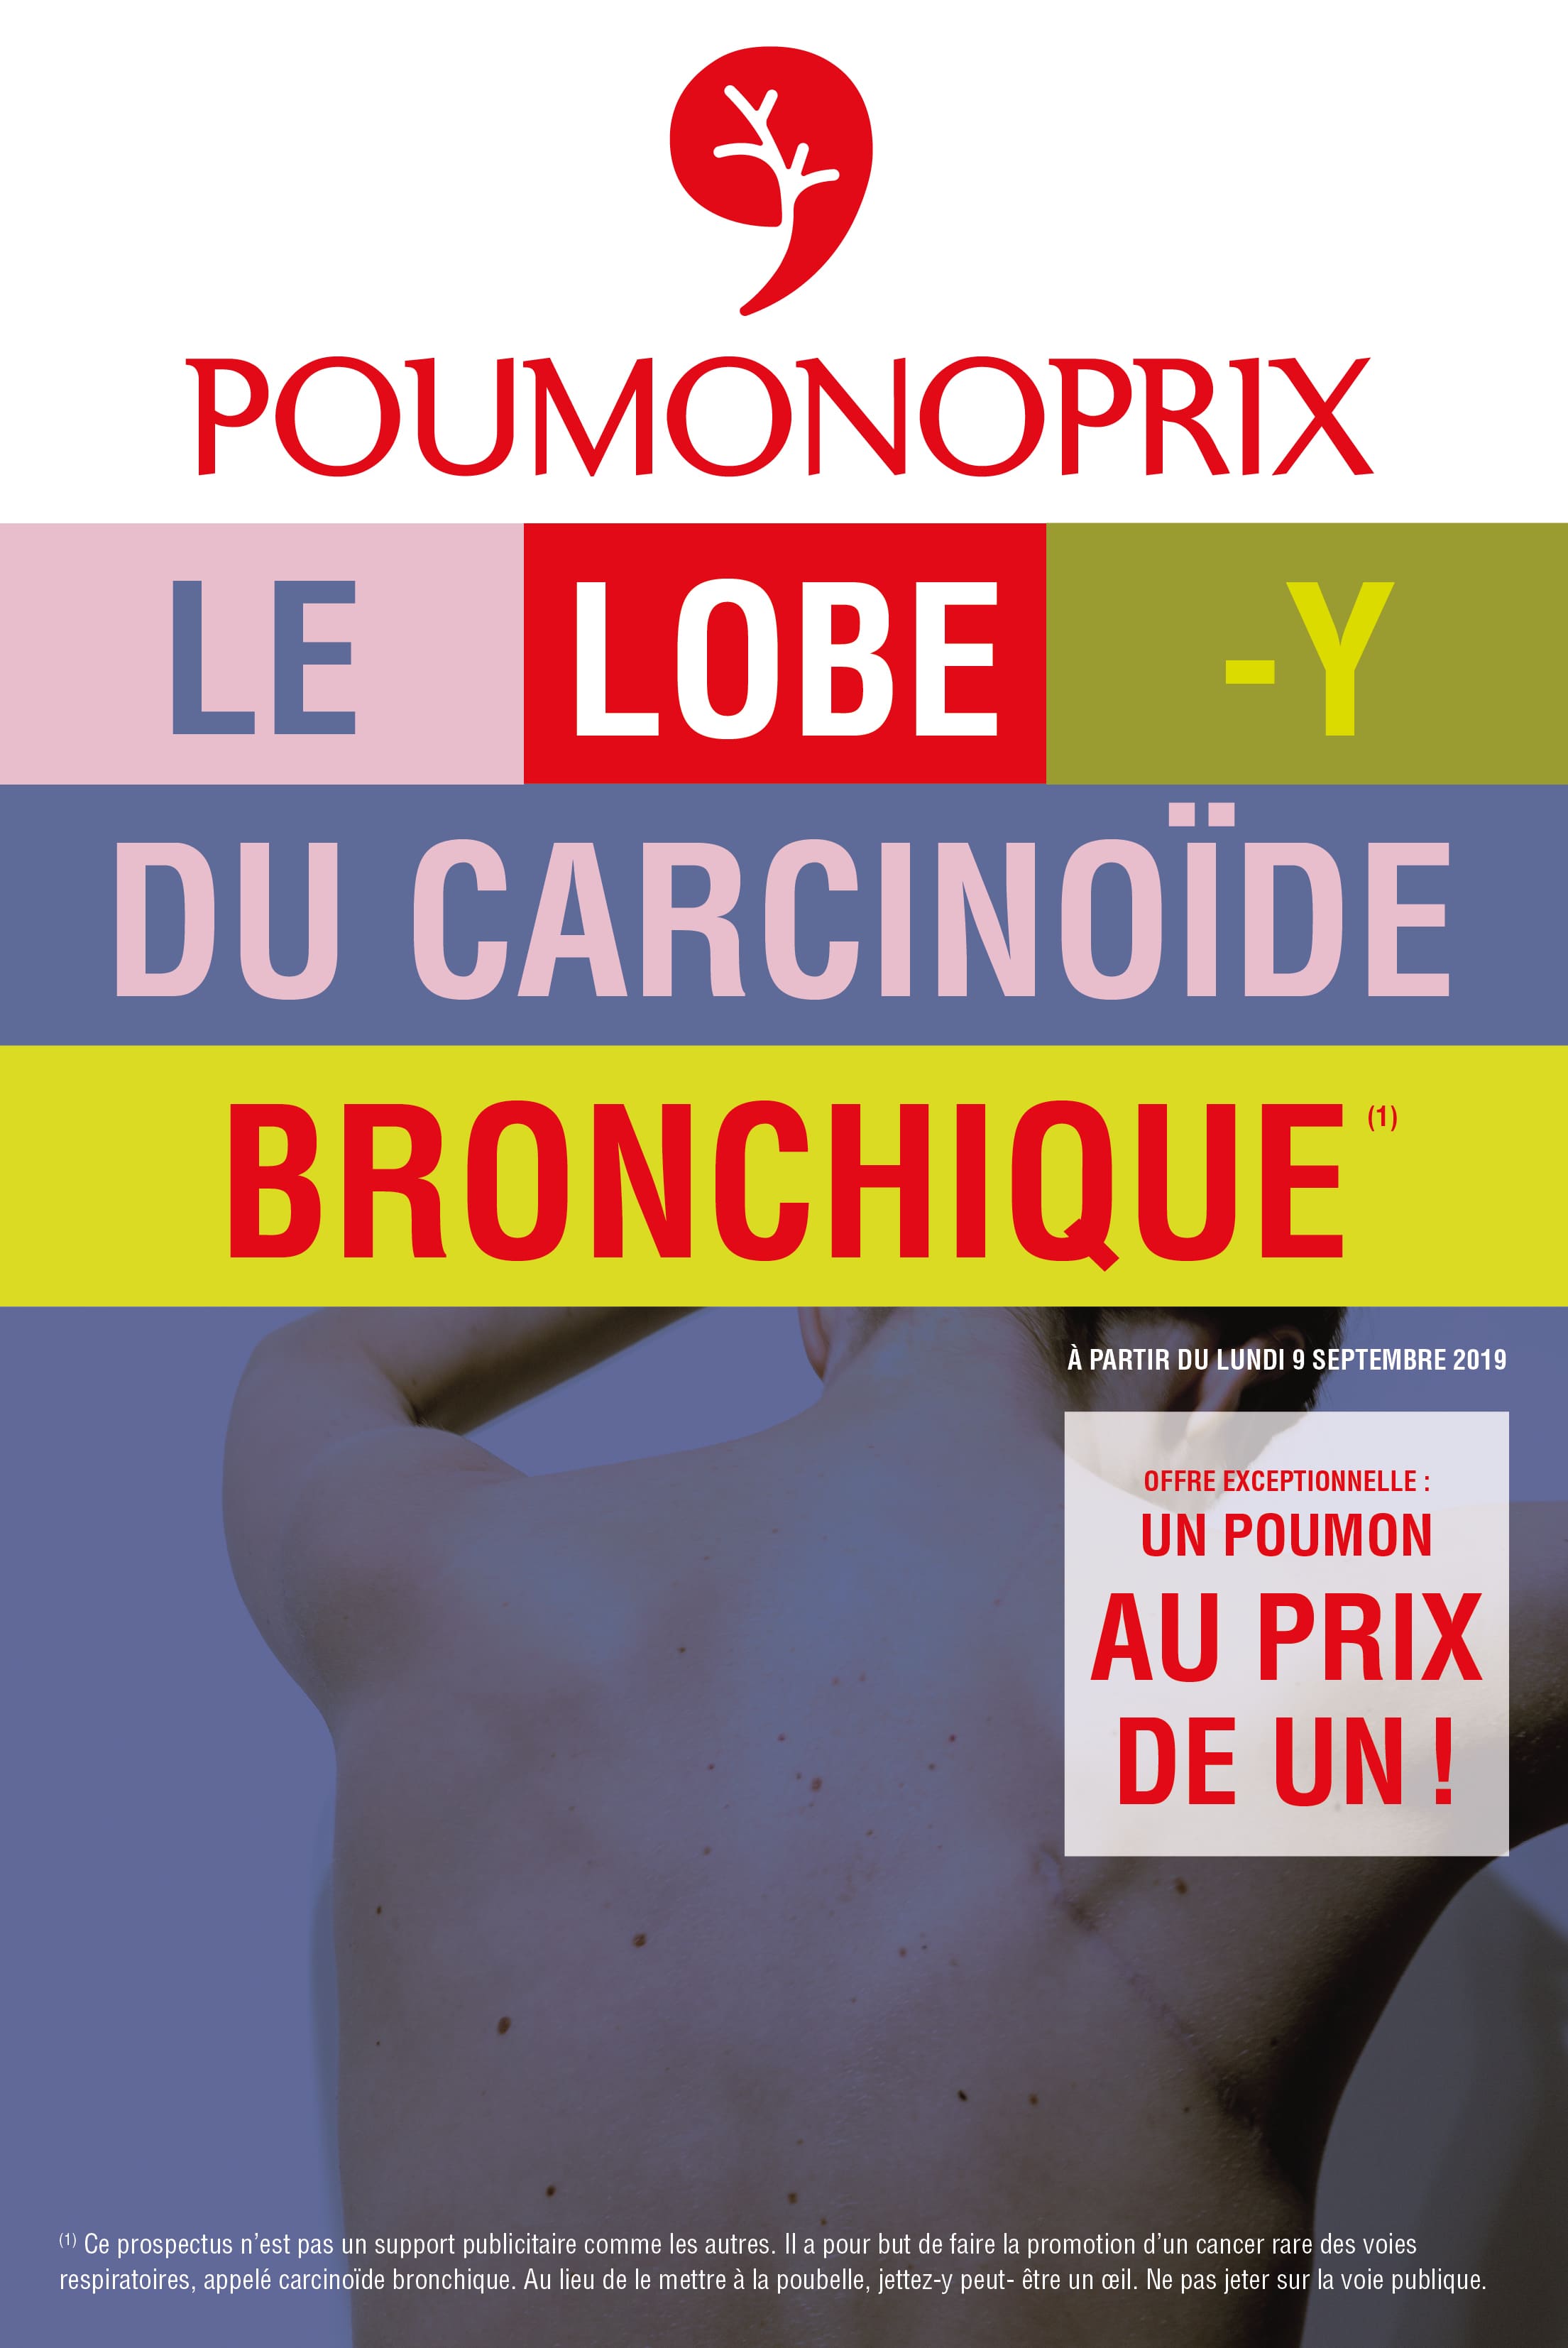

Suite à cette heureuse nouvelle, je décide rapidement de mettre mes compétences en design graphique et en illustration au service des acteurs de la santé et du bien-être. Du cancer, plus particulièrement. C’est une évidence, et je choisis de la convertir en mission de vie. De cette décision naîtra Poumonoprix, un projet artistique à but non lucratif, dont l’ambition est de faire connaître les tumeurs neuro-endocrines bronchiques au grand public, de constituer une ressource pour de futurs malades et de devenir une véritable communauté d’échange et d’entraide autour de ce cancer. Aujourd’hui, je suis à la recherche de donateurs, privés comme publics, qui voudraient bien m’aider à concrétiser Poumonoprix au travers d’une exposition itinérante en France et d’une brochure imprimée.